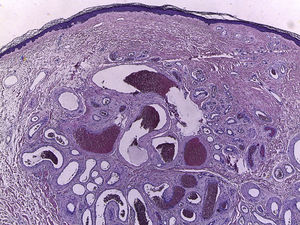

El estudio histopatológico mostró una proliferación bien circunscrita, pero no encapsulada, de vasos agregados en la dermis, revestidos por una hilera única de células endoteliales sin atipia. Unos vasos presentaban una pared fibromuscular gruesa, sin definitiva presencia de lámina elástica, y otros vasos una pared más delgada.

Desde el punto de vista histopatológico se caracteriza por ser una proliferación bien circunscrita en dermis papilar, compuesta por múltiples espacios vasculares de paredes gruesas intercalados con otros de paredes finas. Se ha propuesto que se trata de una proliferación hamartomatosa del plexo subpapilar3,4.